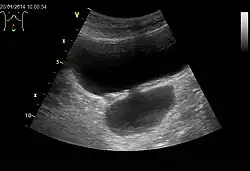

Die Harnblase ist bildgebend mittels Sonographie, Röntgen, Kernspintomographie, Computertomographie und endoskopisch darstellbar. Bildgebung der ersten Wahl sind die Verfahren ohne Röntgenstrahlung, zumeist die Sonographie.

Die Röntgendarstellung der Harnblase heißt Zystographie. Da Weichteile auf Röntgenbildern prinzipiell kaum erkennbar sind, wird beispielsweise zur Füllung triiodiertes Kontrastmittel verwendet. Diese Technik kann so auch Blasendivertikel, Tumoren und nicht röntgenkontrastgebende Fremdkörper sichtbar machen, Hauptanwendung eines Miktionszystourethrogrammes ist die Suche nach einem Reflux, VUR.